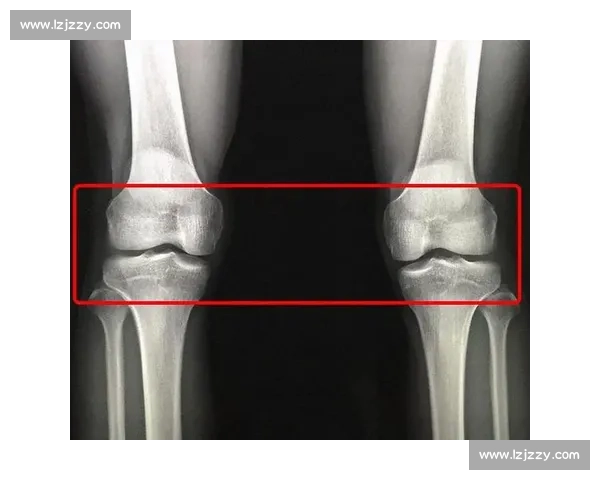

- 骨龄检测:建议先到三甲医院进行左手腕 X 光片检查,通过 Greulich-Pyle 图谱评估骨龄。若骨骺线未闭合,可在医生指导下进行生长激素激发试验。